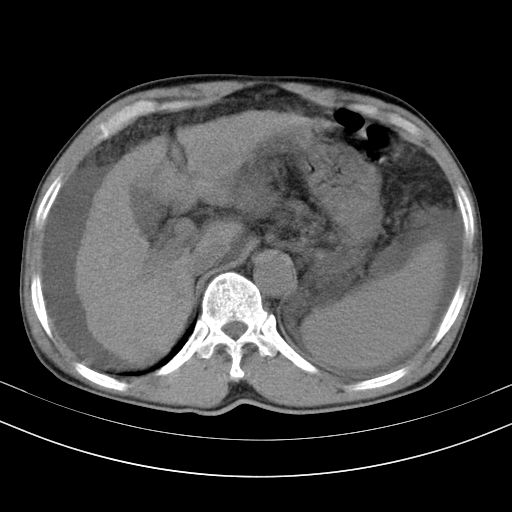

以下是引用随光逐影在2010-2-28 10:23:00的发言:[br]1)考虑肝癌;建议行ct增强扫描检查。2)肝硬化,脾大,腹水。3)慢性胆囊炎。